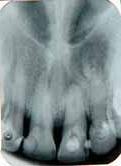

Radiographic evaluation of the involved tooth indicated a normal canal configurations of canals. (Figure 1)

Endodontic access was carried out under local anesthesia and rubber dam isolation. Four canals were detected following access preparation, two each in distal and mesial root. After debridement of the pulp chamber, some pulp tissue remained at the isthmus of mesial orifices. Further, careful probing in the isthmus area with an endodontic explorer revealed an intermediate canal. (Figure 2). Distal angulation working length radiograph showed three distinct canals mesially and two canals distally joiningat the apex. (Figure 3). All the five canals were negotiated and working length was determined. Cleaning and shaping was performed using crown down preparation with Profile nickel titanium rotary instrument (Maillefer, Dentsply), along with copiousirrigation of sodium hypochlorite and RC Prep (Premier,USA). On the second visit, master cone selection was made and obturated by lateral condensation procedure. The patient was recalled for check up and after a week, the tooth was restored with a permanent restoration. (Figure 4). The patient was followed up for two years.

Figure 1- Pre operative radiograph showing distal caries. Figure 2- Pulp chamber floor showing three independant mesial and two distal orifices. Figure 5- Pre operative radiograph showing mesial root and a distal root with an additional indistinct distolingual root. Figure 6- Pulp chamber showing three mesial and two distal canal orifices. Figure 7- Working length radiograph taken with distal shift technique. Figure 8- Post operative obturation radiograph showing three mesial and two separate distal roots. Figure 3 - Working length radiograph reveals three canals in the mesial root and two canals in the distal root. Figure 4- Post operative obturation radiograph.